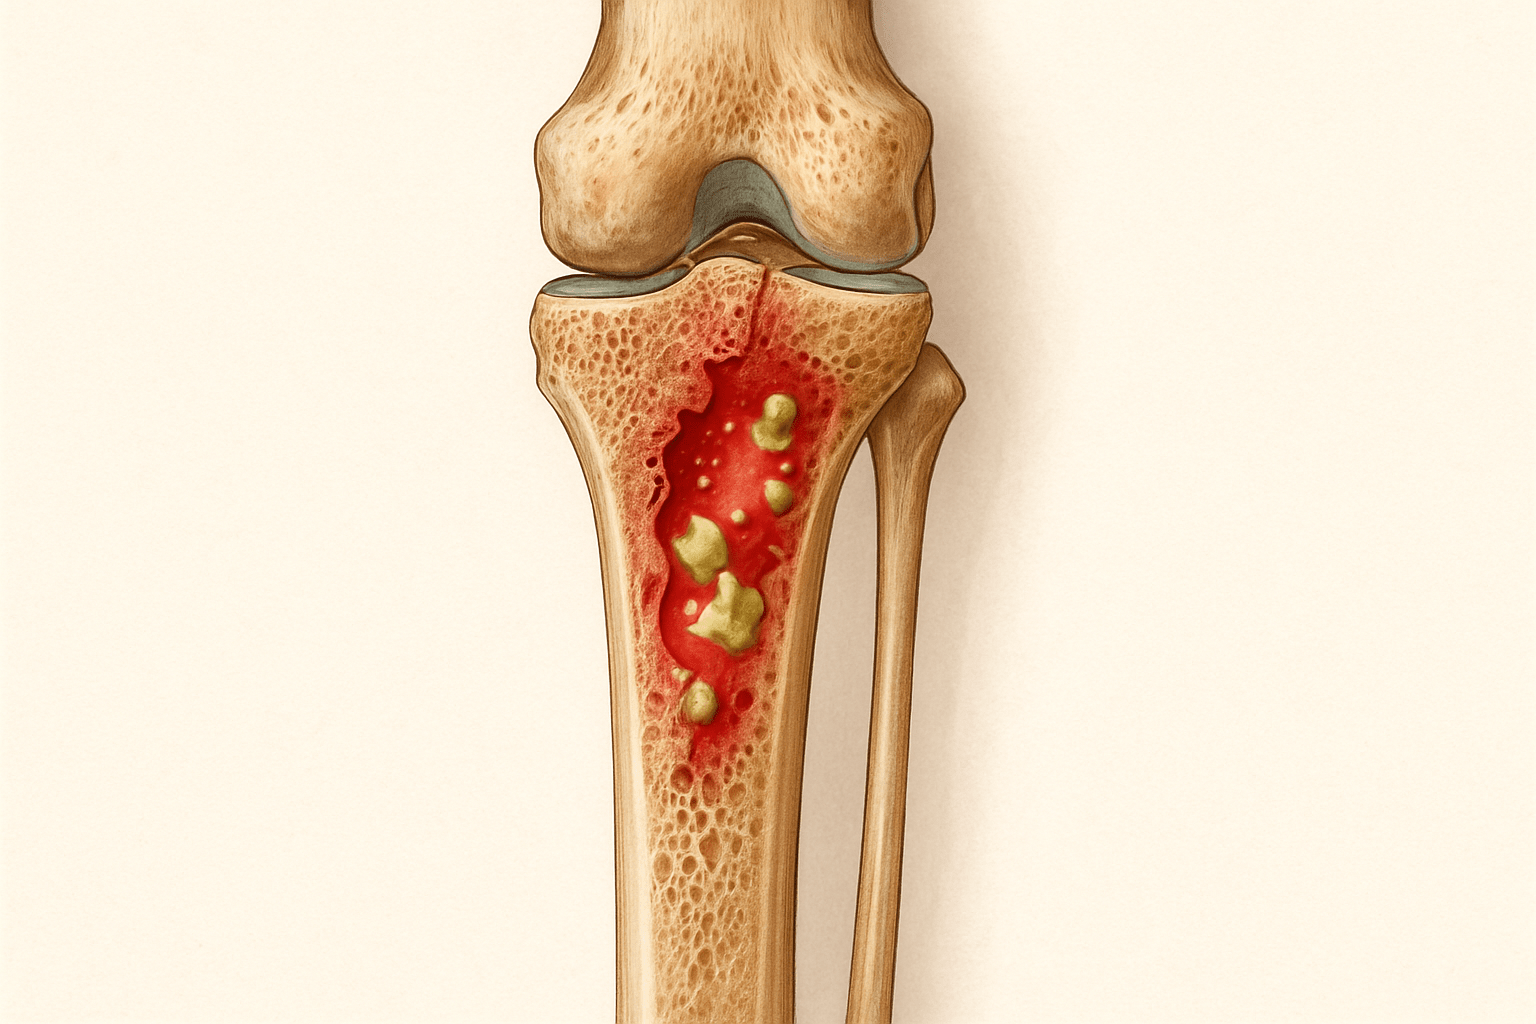

Остеомиелит представляет собой воспалительное заболевание костной ткани, вызванное инфекцией. Это состояние может возникнуть в любой кости, но чаще всего затрагивает длинные кости, такие как бедренная или голеностопная. Основной причиной остеомиелита является проникновение бактерий, чаще всего стафилококков, которые могут попасть в кость через раны, кровь или соседние ткани.

В некоторых случаях может потребоваться операция для удаления некротических участков или дренирования гнойных образований. Хирургическое вмешательство помогает избавиться от источника инфекции и способствует более быстрому восстановлению. После операции может быть назначен также курс антибиотиков для предотвращения рецидивов заболевания.